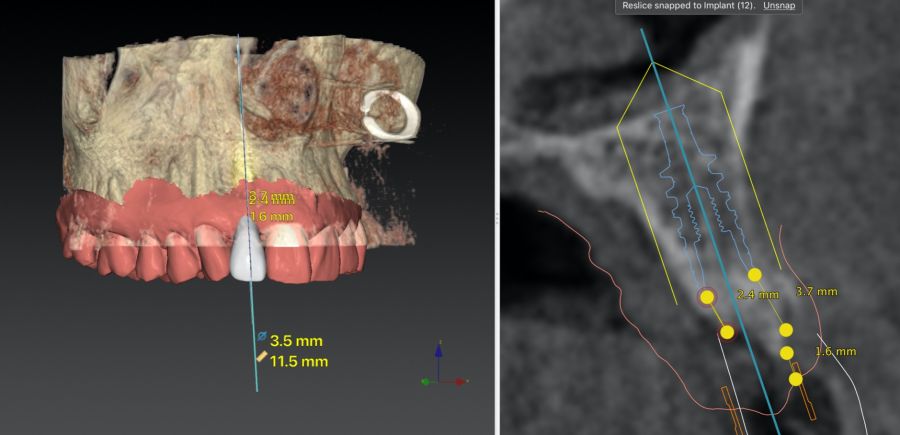

* Phase II: healing proceeded without complications. After 5 months from the alveolar preservation surgery, guided implant surgery was planned at position 1.2 (Figure 2). For this purpose, a DICOM file from cone beam computed tomography (CBCT) and an STL file obtained from scanning with an intraoral optical scanner were used. Using this information, a dental support surgical guide was fabricated (Figure 3). The surgical guide was anchored onto the teeth and guided the preparation of the implant bed and the placement of the implant. The guided surgery technique consisted of flap surgery, preparing and inserting the implant (3.5 x 11.5 mm) according to the standardised Nobel Active® guided surgery protocol (Nobel Biocare AB, Gothenburg, Sweden). Once implant 1.2 was placed,a gingival graft composed of epithelium and connective tissue from the palatal masticatory mucosa was obtained. Subsequently, the superficial epithelial layer of this graft was deepithelialised extraorally using a 15C scalpel blade in order to obtain a connective tissue graft from the underlying layer18.

The de-epithelialised graft was inserted and

positioned buccally and occlusally using horizontal mattress sutures with 5-0 non-resorbable suture (Figure 4)19.